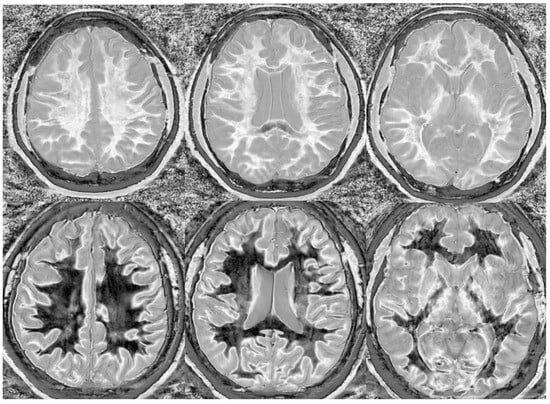

Particularly encouraging, however, is anecdotal evidence that generalized white matter changes detected with dSIR sequences are reversible. Imaging in a patient following chronic methamphetamine use showed widespread white matter changes, which resolved following a prolonged period of abstinence (Figure 18). A similar reversibility was seen in a symptomatic patient following an mTBI (Figure 19). Imaging in the days following injury showed diffuse white matter changes which, along with the symptoms, resolved within two weeks.

Figure 18.

Divided Subtracted Inversion Recovery (dSIR) in a patient methamphetamine user. Narrow middle domain dSIR images at the level of the centrum semiovale (left), corona radiata (middle), and basal ganglia (right) in a volunteer immediately after a methamphetamine binge (top row) and 4 months into abstinence (bottom row) TIshort = 350 ms. TIlong = 500 ms. TE = 7 ms, TR = 5000 ms. The top row images show the “white out” sign, indicating diffuse mild white matter T1 elevation. The signal in the white matter partially normalizes on the bottom row. The appearance is closer to intermediate than normal, but there is definite improvement.

Figure 19.

Divided Subtracted Inversion Recovery (dSIR) in a patient with a mild traumatic brain injury. Narrow middle domain dSIR images at the level of the centrum semiovale (left), corona radiata (middle), and basal ganglia (right) in a volunteer within five days of an mTBI (top row) and two weeks later (bottom row). TIshort = 350 ms. TIlong = 500 ms. TE = 7 ms, TR = 5000 ms. The top row images show the “white out” sign, indicating diffuse mild white matter T1 elevation. The signal in the white matter normalizes on the bottom row, where it appears normal.